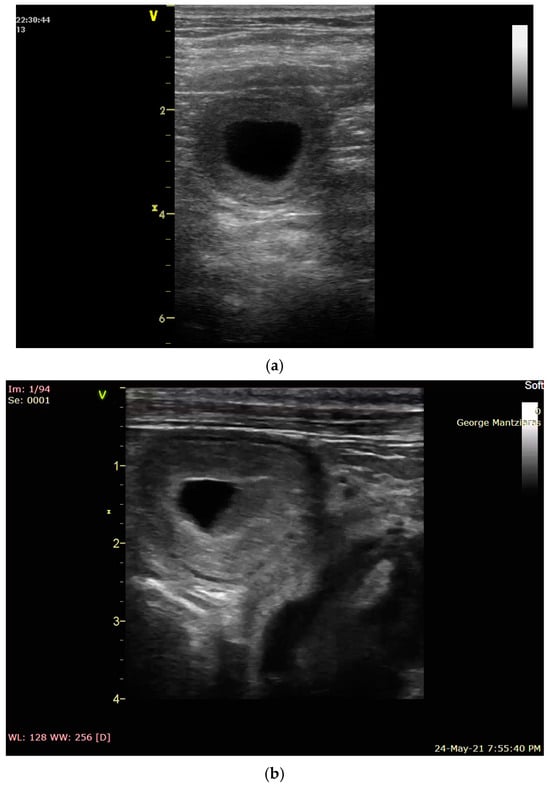

- Yeager, A.; Mohammed, H.; Meyers-Wallen, V.; Vannerson, L.; Concannon, P. Ultrasonographic appearance of the uterus, placenta, fetus, and fetal membranes throughout accurately timed pregnancy in beagles. Am. J. Vet. Res. 1992, 53, 342–351. [Google Scholar] [CrossRef]

- England, G.C.W.; Allen, W.E. Studies on canine pregnancy using B-mode ultrasound: Diagnosis of early pregnancy and the number of conceptuses. J. Small Anim. Pract. 1990, 31, 321–323. [Google Scholar] [CrossRef]

- England, G.C.W. Ultrasound evaluation of pregnancy and spontaneous embryonic resorption in the bitch. J. Small Anim. Pract. 1992, 33, 430–436. [Google Scholar] [CrossRef]

- England, G.C.W. Ultrasonographic assessment of abnormal pregnancy. Vet. Clin. N. Am. 1998, 25, 849–868. [Google Scholar] [CrossRef]